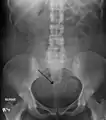

الفحص باليدين قادر على تحديد وجود الأورام كبيرة الحجم، يعد استخدام الموجات فوق الصوتية أداة التشخيص المثالية لتقدير وجود الورم. يصف التخطيط بالموجات الصوتية الورم على أنه كتل بؤرية غير متجانسة النسيج، والتي تؤدي إلى تظليل في الإشعاعات فوق الصوتية، ويمكن تحديد موقع وأبعاد الورم، كما يمكن استعمال التصوير بالرنين المغناطيسي لوصف الورم وأبعاده وموقعه في الرحم. طرق التصوير لا يمكنها التمييز بدقة بين الورم الخبيث والحميد، على الرغم من أن الورم الخبيث يعد نادرا. النمو السريع أو المفاجئ بعد انقطاع الطمث سوف يزيد الشك من وجود ورم خبيث في الرحم، وقد يكون هناك آثار غزو للأنسجة المحيطة. نادرا ما يتم أخذ خزعة للتشخيص، وإذا تم أخذها، فإنها لا تكون تشخيصية، واذا لم يكن هنالك تشخيص واضح بعد التصوير، يتم الإيعاز بالجراحة . ومن طرق التصوير الأخرى التي لها أهمية في تقييم الورم الذي يؤثر على التجويف الرحمي: تصوير الرحم وقنوات فالوب، والتصوير بالموجات الصوتية بعد ملئ الرحم بسائل .

ورمان ليفيان عضليان متكلسان في الرحم.